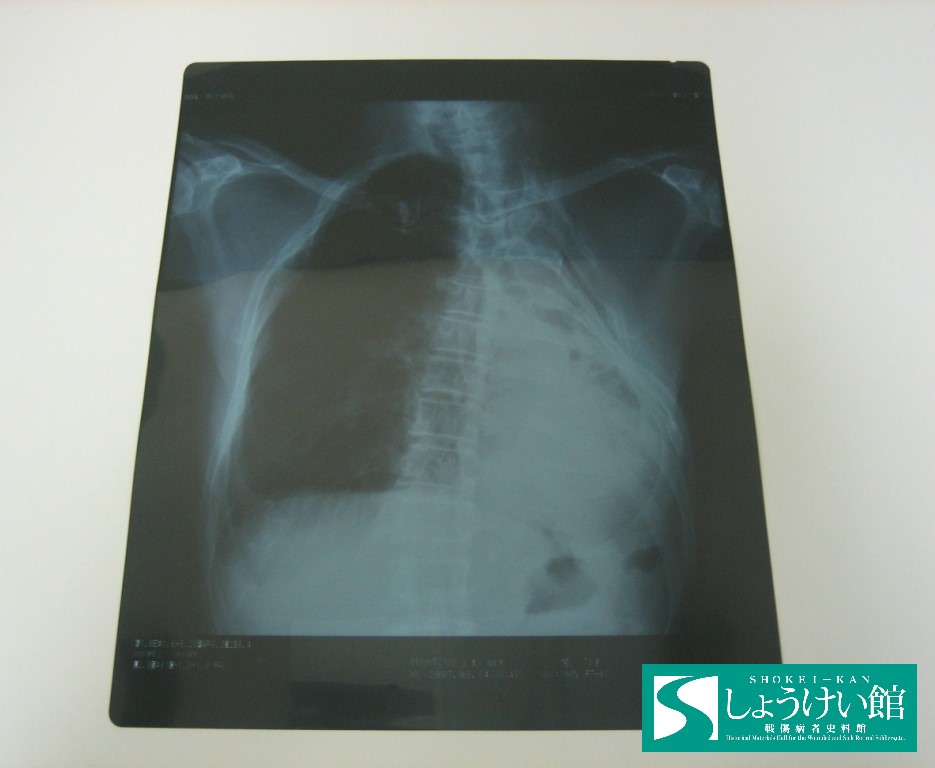

肺のレントゲン写真

海軍に志願、レイテ沖海戦では助かったものの、疲労のために結核にかかってしまった戦傷病者のレントゲン写真。結核治療で片肺を切除したことがはっきりと映っています。